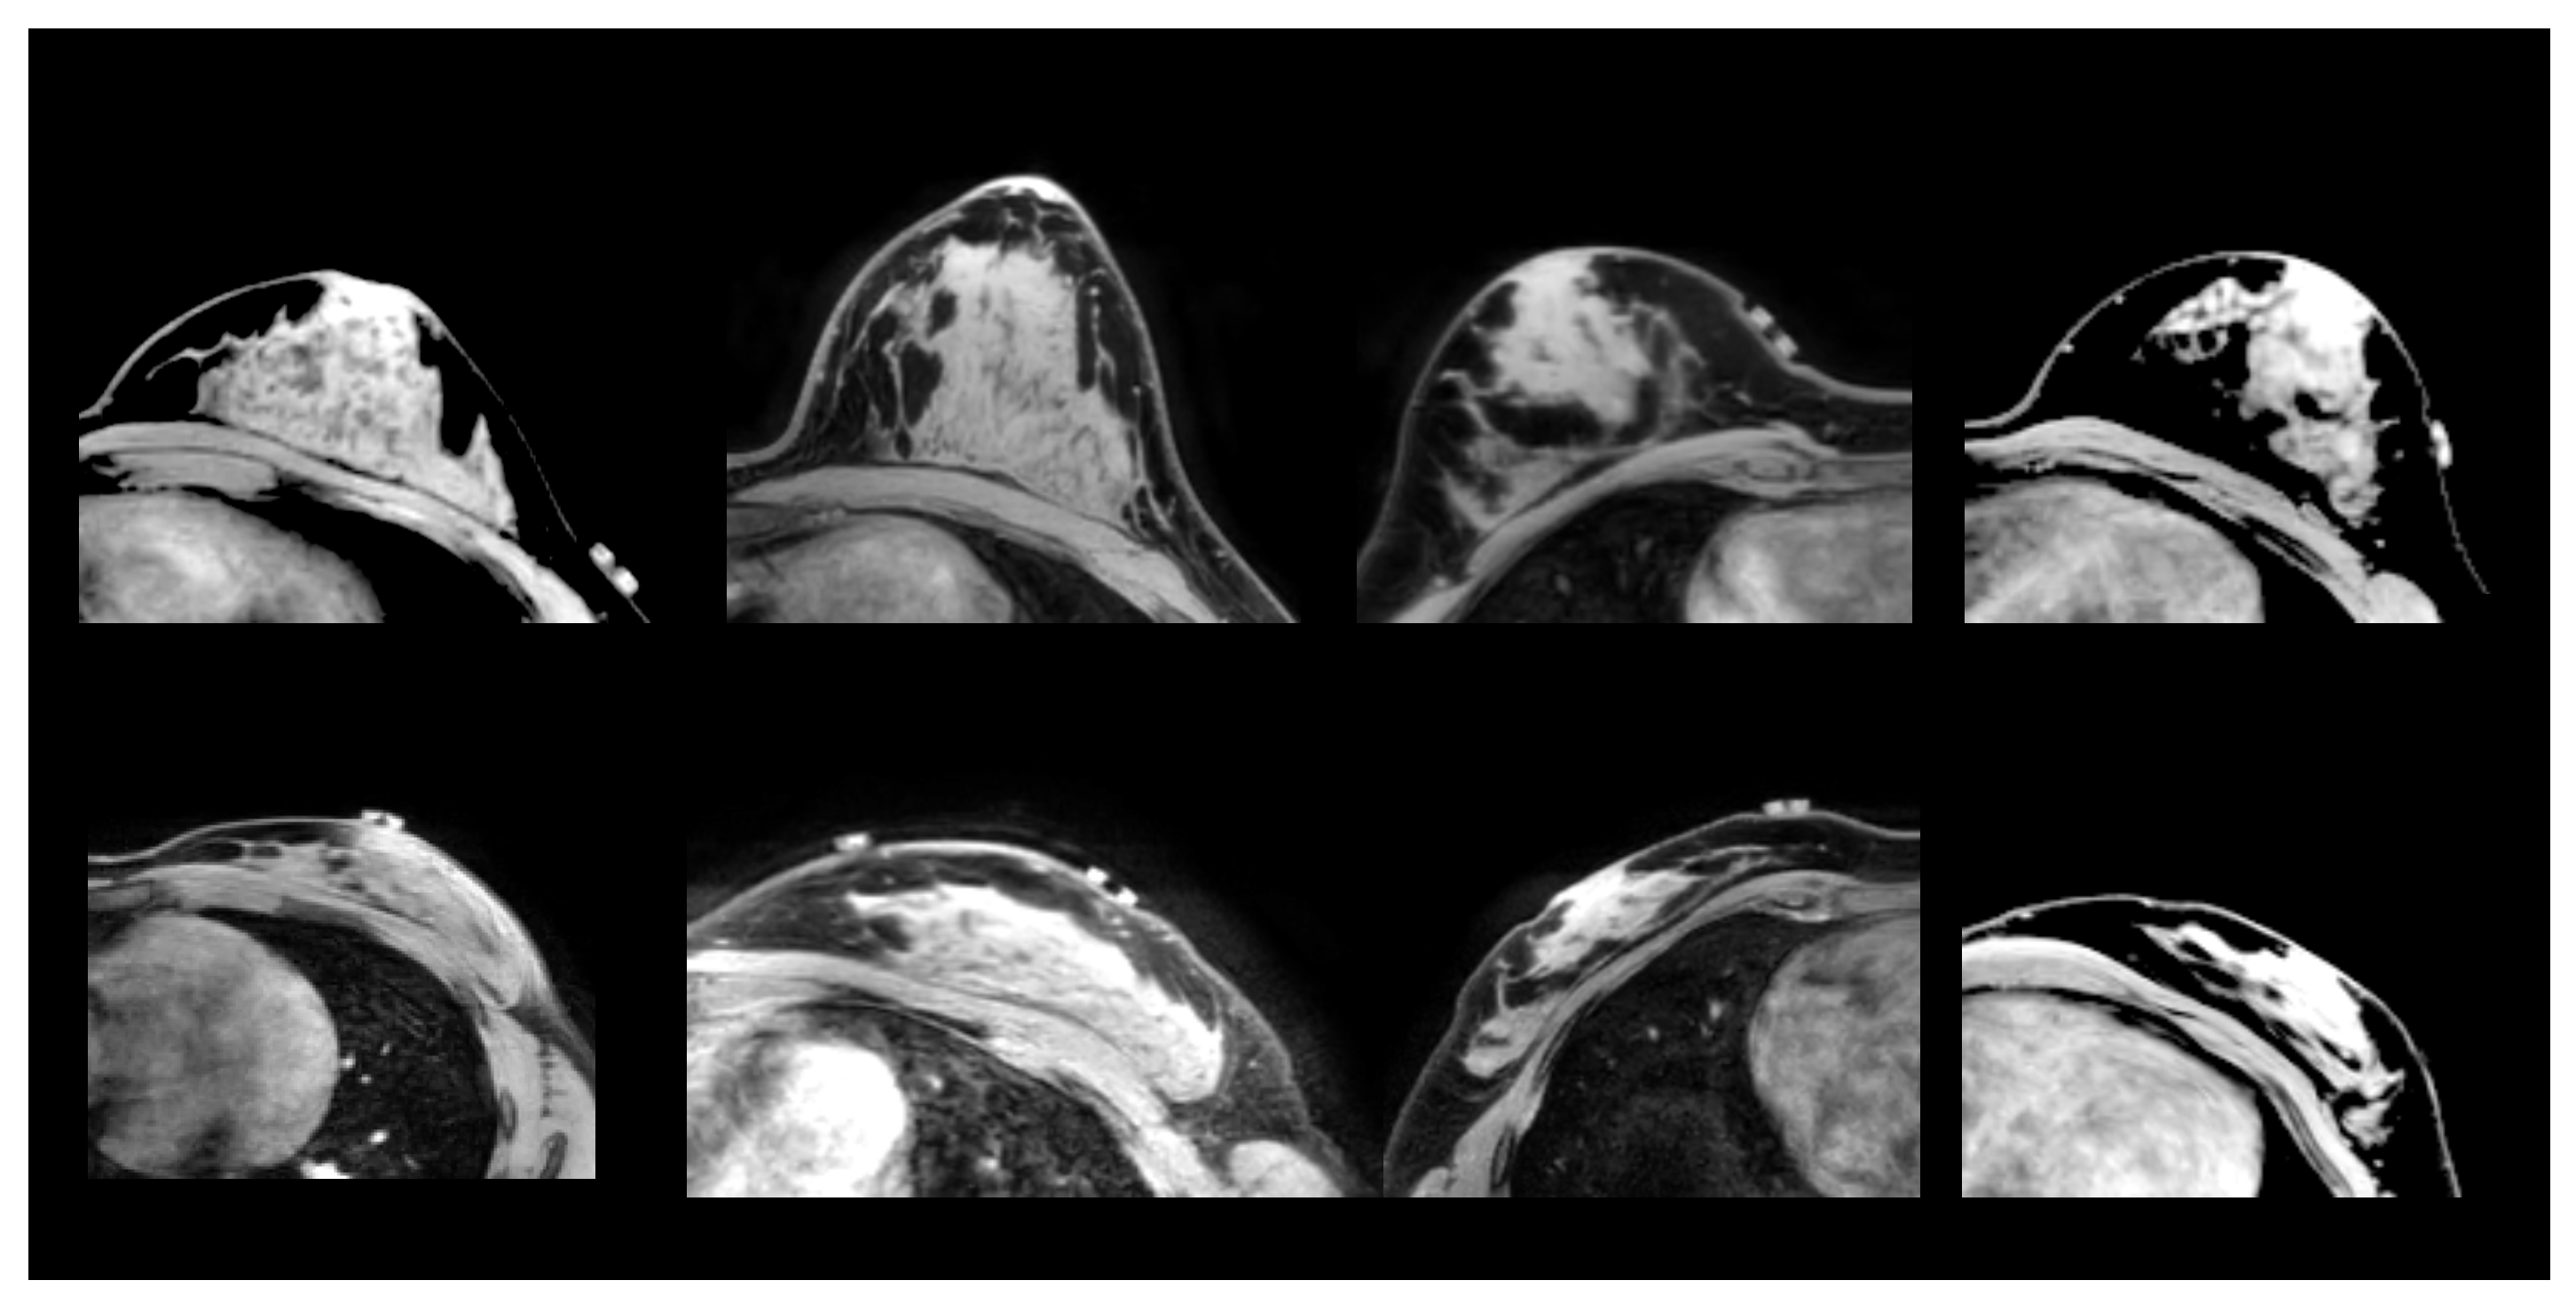

2.1.1. Prone-Prone

2.1.2. Prone-Supine